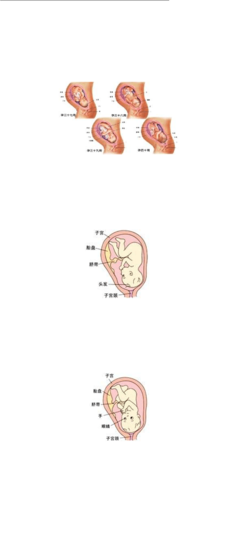

为了让我看上去好看一些,我还长出了指甲和头发。然而,我的住房条件越来越差了,我索性不像以前那样总是动来动去的,渐渐变胖的我,有点儿懒了,因为我的双腿已经只能蜷着伸到自己的胸部了,妈妈我在里面这种姿势也是好累的感觉哟,呵呵,但我已经习惯了。

近9个月的时候,我遭遇了一件非常可怕的事情,我的身体倒转过来了!我的小脑袋进入到妈妈的骨盆了。我很想再把自己转回去,可是不管我怎么努力,我都做不到!我有点担心,因为这样仰着才开始我也不是很习惯,还好我的适应能力非常好,现在对我来说无论怎么样我都能适从,我知道可能我快要与爸爸妈妈见面了吧,呵呵,那我真是太开心了……

第九个月——万事俱备

妈妈,我已经是一个足月的婴儿了。呼吸、消化、生殖系列、大脑、骨格、四肢、五官……无论你从哪一点看,我都是一个完完整整的婴儿!当妈妈每次去医院做检查的时候,医生总会将我的位置情况告诉她,人们给我坐的姿式起了一个很有趣的名字叫“胎位”。据说我的坐姿将直接影响到我出生的过程是否顺利。

入盆以后,我的身体一直是倒过来的,我的头被紧紧地夹在一个小小的通道里;而我的房子也小得让我几乎转不过身,这种日子真不好过。看来这里算是呆不下去了,我要搬家!